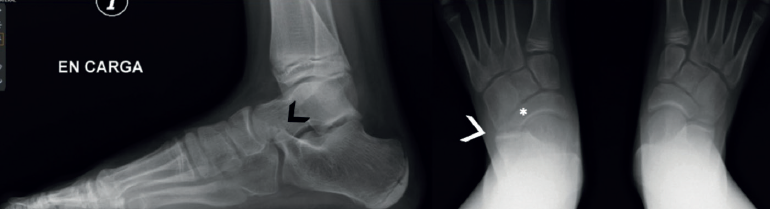

Las radiografías simples deben ser siempre bilaterales. Se deben solicitar: anteroposterior (AP) en carga, lateral en carga y oblicua a 45°. La radiografía a 45° descrita por Sloman en 1921(39) demuestra la presencia de coaliciones CN en el 90-100% de los casos(40,41). Es cierto que la superposición de los huesos del tarso dificulta el diagnóstico de la coalición, pero se han descrito algunos signos distintivos directos e indirectos que ayudan al diagnóstico, siendo los más conocidos el signo del oso hormiguero, el pico del astrágalo (talar beak) y el signo de la C. Estos signos clásicos muestran una buena especificidad, pero una sensibilidad moderada: el hecho de que la coalición sea fibrosa, cartilaginosa u ósea, y el tamaño variable de la coalición influirán en la imagen y en nuestra capacidad de diagnóstico.

El hocico del oso hormiguero es diagnóstico de una coalición CN. Inicialmente descrito en las radiografías oblicuas, también puede ser visible en las proyecciones laterales(37,42,43)(Figura 6A). El proceso anterior del calcáneo normalmente es triangular, pero se alarga en las coaliciones y la punta es cuadrada como el hocico de un oso hormiguero. Un estudio de Crim y Kjeldsberg(22) demostró en radiografías laterales una sensibilidad del 72% y una especificidad del 90% del signo del oso hormiguero, y del 90-100% de los casos en las oblicuas(40,41). Será incompleta en caso de fibrocartilaginosa y completa en las uniones óseas.

El hocico del oso hormiguero inverso: en la radiografía AP en carga del pie, se verá el proceso lateral del escafoides más alargado (Figura 6F, flecha). Normalmente los márgenes están alineados con la cabeza. En las coaliciones, el borde lateral tiende a estar más alargado (Figura 6B, asterisco), en algunos casos su borde es cuadrado y parece articular con el calcáneo. La sensibilidad original reportada de este signo fue del 50% y la especificidad fue del 100%(22), aunque un informe posterior encontró una sensibilidad de tan solo el 18%(44).

El pico del astrágalo (talar beak) se produce secundariamente por la rigidez del retropié(45). La articulación de Chopart aumenta su movilidad a dorsal, el escafoides sube por encima de la cabeza del astrágalo creando con la tracción capsular un pico (es más común en las TC que en las CN) (Figura 7).

El signo de la C o C-sign es el signo directo más fácil de identificar en la vista lateral. Analizando la faceta medial de la articulación subastragalina en las coaliciones TC, que son las más frecuentes (Figuras 7 y 8). Si es distrófico o la línea articular es irregular, sugiere osteoartritis. Los pacientes suelen ser jóvenes al diagnóstico. Posteriormente, en caso de sinostosis con continuidad entre el calcáneo y el astrágalo, un bloque óseo une la voluminosa faceta medial distrófica al sustentaculum tali. Tiene la forma de un arco convexo posteriormente: de ahí el “signo de la C”(45). En pies planos puede ser positivo sin coalición(46) (sensibilidad del 88% y especificidad del 87%)(22).

La ausencia de la faceta medial (subastragalina) precisa de una proyección exacta lateral centrada en el retropié(22). Si la articulación subastragalina posterior es visible y bien alineada, la anterior debiera ser igualmente visible; si no, es posible una coalición(22,47) (sensibilidad del 72-100% y especificidad del 42-94%) (Figura 8A).